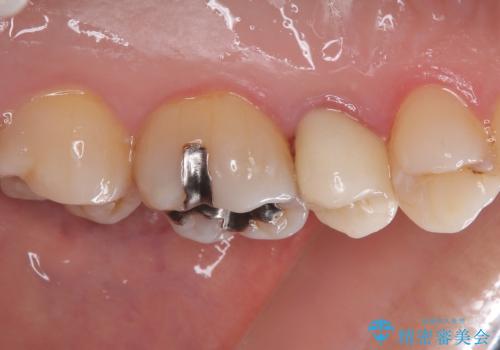

- むし歯と銀歯を気にして来院された患者様です。

銀歯の歯は既に根管治療がされており、根尖部に病変が認められないため、根管治療を行うことなくオールセラミッククラウンにて補綴治療を行うこととしました。

むし歯の症状のある歯は、ややしみることがある程度でしたが、レントゲン写真では非常にむし歯が大きく、神経組織に迫っている状態でした。

術前診査では神経を全て取る可能性は低いと予想されましたが、一部切除する可能性があることを伝えた上で治療を行うこととしました。

やはりむし歯は大きく、一部歯髄を切除することとなりましたが、その後は良好な経過をたどっています。